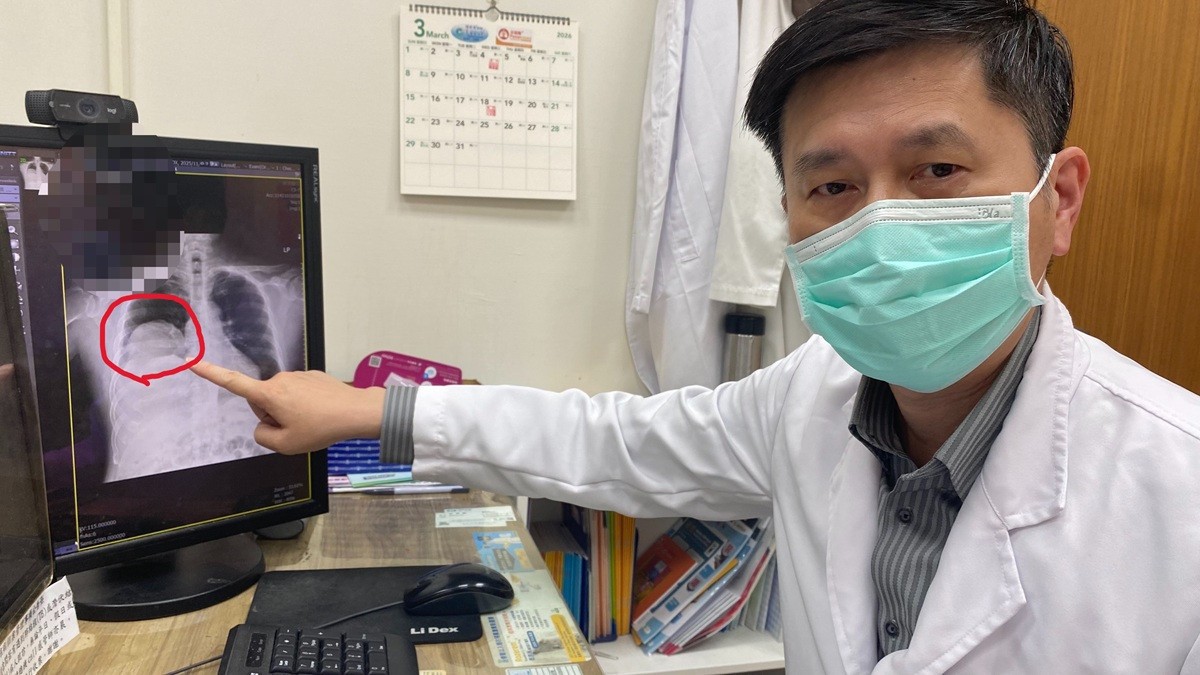

住院期間,患者仍頻繁出現低血糖發作,甚至血糖多次低於30 mg/dL,需持續補充高濃度葡萄糖維持穩定。進一步透過胸部X光與電腦斷層檢查,發現右肺有一顆巨大腫瘤,影像顯示約15×11公分,且壓迫周邊結構,並伴隨肋膜積液與淋巴結腫大情形。

因此會診胸腔內科醫師涂川洲副院長,醫療團隊評估後高度懷疑為「腫瘤相關低血糖」,可能與腫瘤分泌類胰島素生長因子(IGF-2)有關,屬於罕見的「非胰島素瘤性低血糖症(NICTH)」。此類情況多見於大型腫瘤,尤其是間質性或纖維性腫瘤。